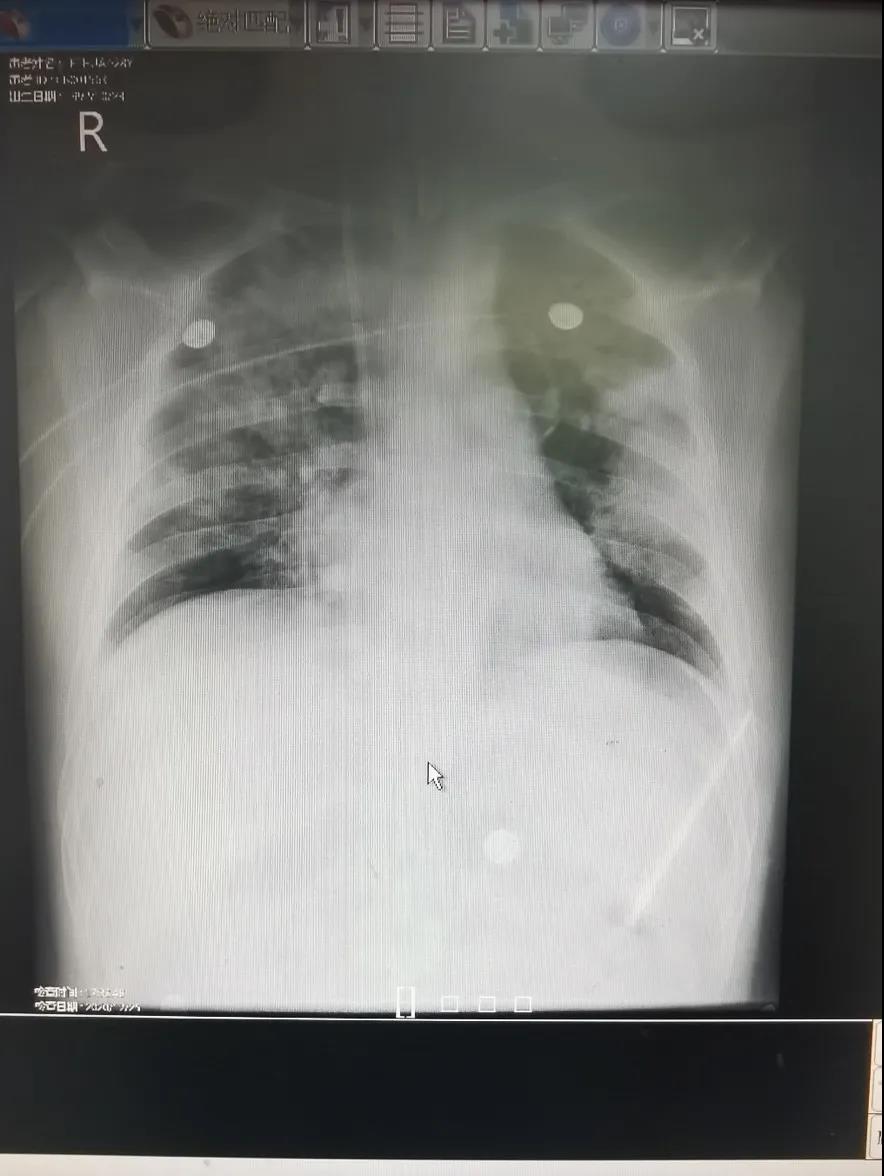

治疗前胸片:双肺多发渗出灶。